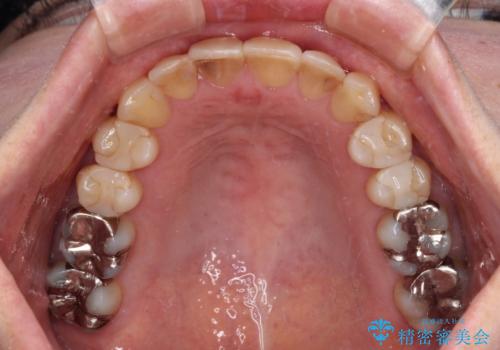

- 矯正装置

- 審美装置

- 治療期間

- 1年10ヶ月

舌突出癖により、上下前歯がなかなか接触せずに治療期間を要しましたが、舌のトレーニングにより無事に治療を終えることができました。